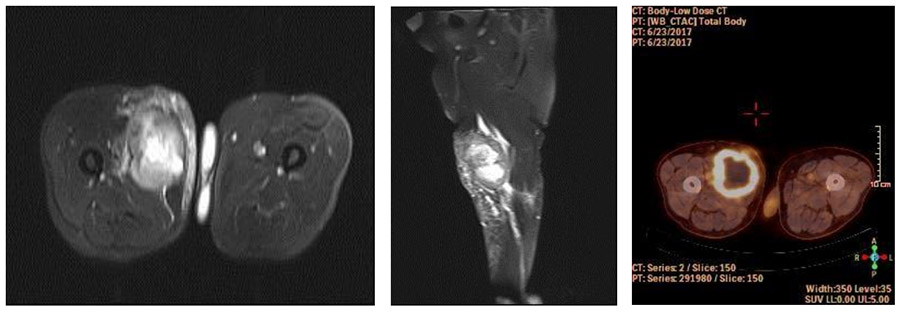

Ameliyat Öncesi: MR’da uyluk iç kısımda düzensiz sınırlı, merkezinde nekroz çevresinde ödemin eşlik ettiği heterojen kitle ile PET’de artmış periferik kontrastlanma görülmekte